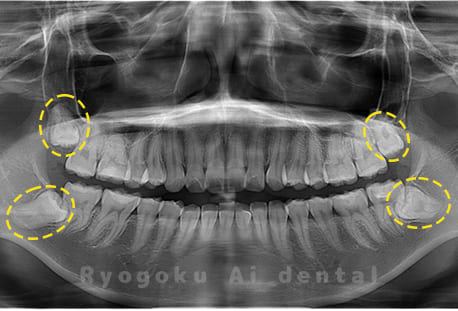

Case04

-

- 原因

- 上顎の親知らず、下顎の水平埋伏の親知らず

- 治療内容

- 上顎の親知らず、下顎の水平埋伏の親知らずを抜歯したケースです。

<リスク・副作用>

手術後は痛み、腫れ、痺れなどの副作用が生じる場合があります。